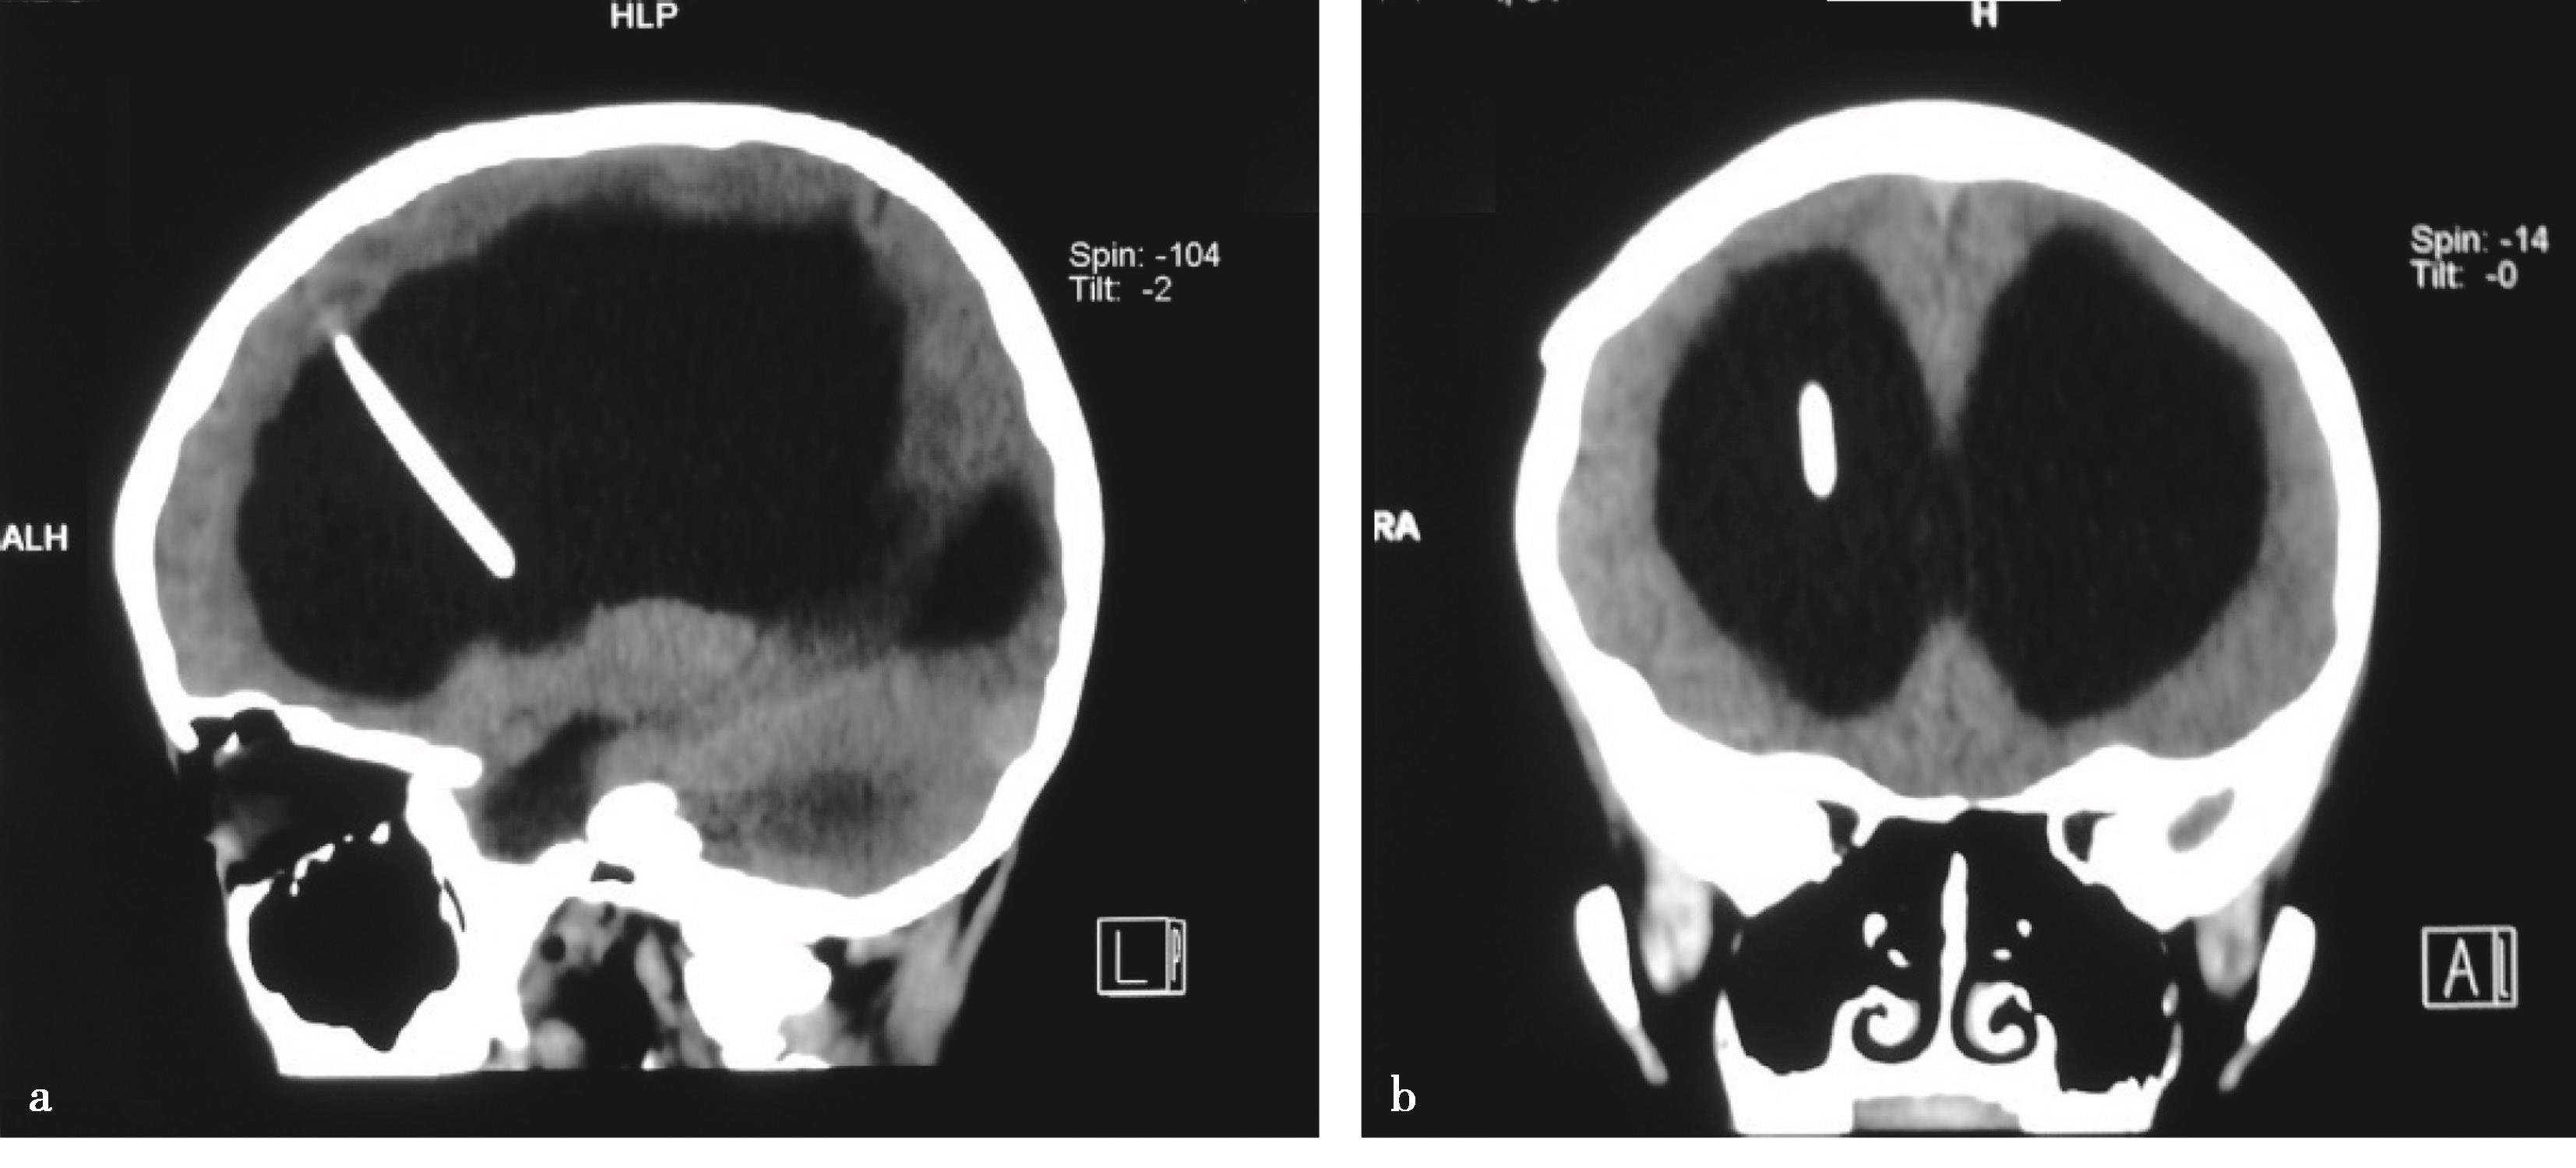

图3-1-4-2 脑室分流管的理想位置

a.CT矢状位见分流管位于侧脑室额角;b.CT冠状位见分流管位于额角略偏向中线;c.内镜下见分流管远端位于室间孔